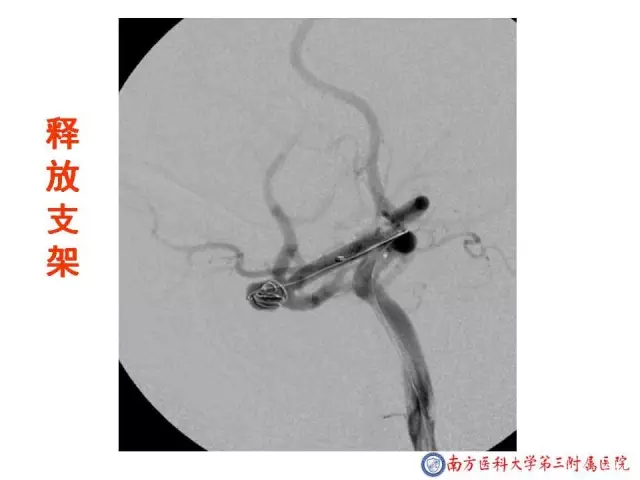

今天为大家分享的是“强生医疗CNV-神经介入专栏”第二十五期,由南方医科大学第三附属医院神经外科主任黄理金教授带来的“Enterprise支架辅助栓塞动脉瘤的优势”精彩讲课视频及PPT,欢迎观看。文章仅代表作者个人观点,如有不同见解,欢迎同道斧正!